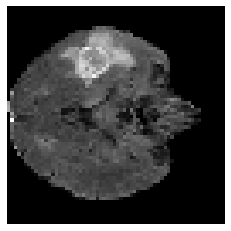

Disentangled representations can be useful in many downstream tasks, help to make deep learning models more interpretable, and allow for control over features of synthetically generated images that can be useful in training other models that require a large number of labelled or unlabelled data. Recently, flow-based generative models have been proposed to generate realistic images by directly modeling the data distribution with invertible functions. In this work, we propose a new flow-based generative model framework, named GLOWin, that is end-to-end invertible and able to learn disentangled representations. Feature disentanglement is achieved by factorizing the latent space into components such that each component learns the representation for one generative factor. Comprehensive experiments have been conducted to evaluate the proposed method on a public brain tumor MR dataset. Quantitative and qualitative results suggest that the proposed method is effective in disentangling the features from complex medical images.